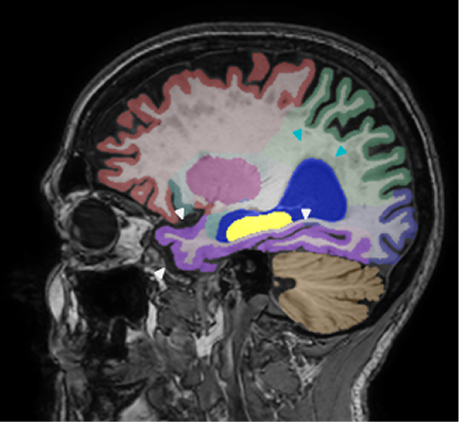

Retrospective brain volumetric analysis in a female patient diagnosed with Alzheimer’s disease at age 77 showed progressive brain atrophy over a 5-year period. The scans demonstrate temporal cortical atrophy with marked ex-vacuo enlargement of the lateral ventricles.

PATIENT

Female patient diagnosed with Alzheimer's Disease at Age 77

Analysis period

5 years

regions of interest

Temporal cortex

Hippocampus

Inferior lateral ventricles

Age 72

Age 74

Age 77

Lateral ventricle